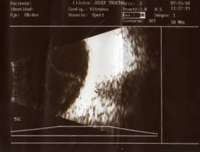

Figura 3. Imagen ecográfica del DR seroso.